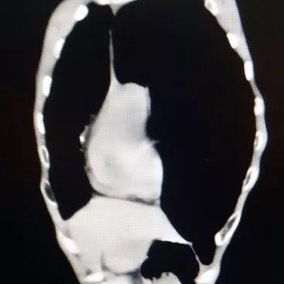

After a preoperative examination, it is observed that the patient's anterior chest wall protruded severely, reaching its peak at the xiphoid process, which presented as a 90-degree angle when viewed from the side. The heart is displaced to the right chest cavity, and the torso is severely deformed, characterized by a broad chest and a noticeably narrowed waist and abdominal area. The narrowing is most pronounced above the pelvis. Moreover, a chest CT scan reveals two large cysts located between the heart and the anterior chest wall in the lower lobe of the left lung, measuring 7x8 cm and 9x10 cm respectively.

We developed and executed a personalized minimally invasive surgical treatment plan for the patient. The Wung procedure and the Wenlin procedure was performed during the operation. First, a 3 cm longitudinal incision was made on the left chest wall to insert a thoracoscope, which was used to explore and remove the cysts on the left lung. Second, another 3 cm incision was made on the right chest wall and two passage tunnels were constructed for the bars between these two incisions. A third tunnel was then constructed near the costal arch, and three pre-shaped bars were inserted into the tunnels to correct the deformity. Lastly, the bars were securely fixed, and the incisions were sutured. The surgery was successfully completed in 2 hours, effectively eliminating the malformation and restoring the chest wall to an almost normal appearance.